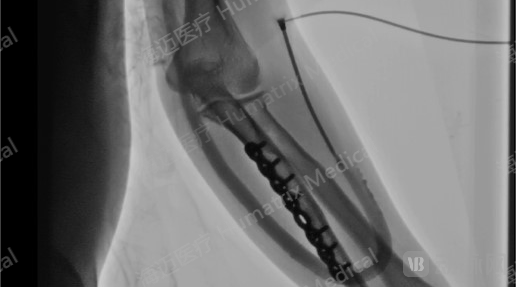

临床试验患者使用LineMatrix耐迈通®生物型人工血管长期血液透析,血管造影通畅